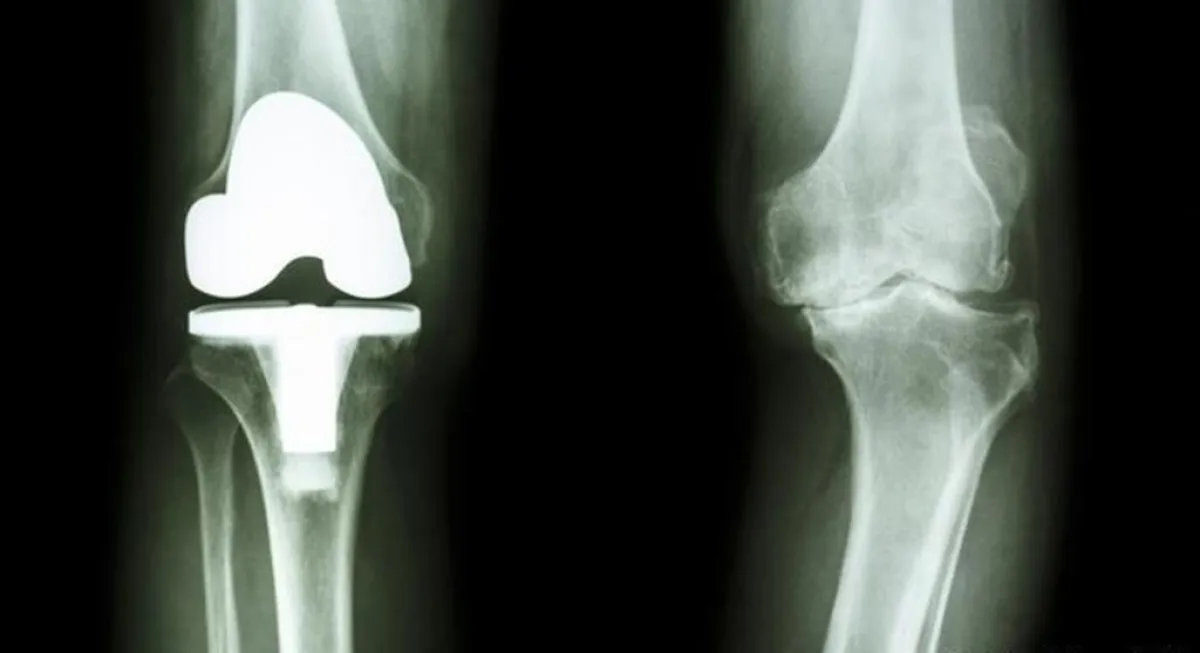

وأكدت وسائل إعلام صينية، وفقًا لـ«روسيا اليوم»، أن الأطباء في المستشفى قاموا بزارعة مفصل مصنوع من معدن «التانتالوم» النادر، المطبوع بتقنيات الطباعة الثلاثية الأبعاد في ركبة رجل يبلغ من العمر 84 عامًا، وقد تمكن الرجل المعمر من تحريك قدمه وثني المفصل بعد يوم واحد فقط من إجراء العملية.

وتكمن أهمية هذه العملية في أنها ستقلل من مخاطر عمليات زراعة الركبة التقليدية، وستفتح مستقبلاً جديدًا في عالم زراعة المفاصل الاصطناعية، وخاصة أن معدن «التانتالوم»، الذي يستخدم في الصناعات الدقيقة وحتى صناعات الطيران، يمتاز بخصائص فريدة تجعله أفضل من باقي المعادن المستخدمة اليوم لإنتاج المفاصل الاصطناعية، بحسب الأطباء.